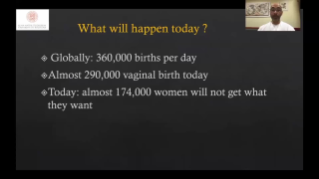

Didukung oleh platform ZST+ yang canggih, solusi cerdas yang lengkap dari Nuewa dirancang secara khusus untuk mendukung kesehatan kaum wanita yang lebih baik selama masa prakehamilan, kehamilan, dan pemulihan pascapersalinan, untuk menghasilkan diagnosis yang komprehensif dan efisien guna memenuhi tantangan klinis yang semakin meningkat.